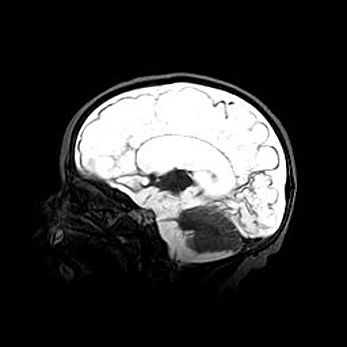

Наружная гидроцефалия с возможной атрофией височных областей.

Возраст: 28 дней

Вес: 3670 г

Пол: мужской

Окружность головы: 38 см

Срок гестации: 40 недель

Гидроцефалия головного мозга у новорожденных – это заболевание, которое характеризуется скоплением избыточного количества спинномозговой жидкости в желудочковой системе головного мозга в результате затруднения её перемещения от места выработки к месту поглощения в кровеносную систему или вследствие нарушения абсорбции. При открытой наружной форме гидроцефалии у новорожденных расширяются и переполняются субарахноидные пространства.

При нормотензивных  формах,  которые,  как  правило,  являются  следствием  перенесенных ишемических  повреждений  паренхимы  мозга,  возможно  сочетание микроцефалии  с нормотензивной гидроцефалией. В основе данных изменений лежит атрофия больших полушарий с преимущественной  локализацией  в  лобно-височных  областях.